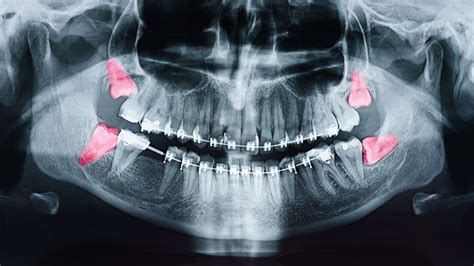

Oct 10, 2019 · wisdom teeth are a third set of molars in the back of your mouth. Without dental insurance, wisdom teeth extractions can cost between $200 and $1,000 per tooth.² if you need all four wisdom teeth pulled, the bill can quickly add up. Aug 12, 2021 · without insurance, wisdom teeth removal can cost $400, but with extras cover, you could pay as little as $80. If your wisdom teeth removal doctor sees that your wisdom teeth are impacted or coming in crooked, getting them out when you are young (when the procedure is less complex) is a wise course of action. Sep 13, 2020 · the cost for wisdom teeth removal surgery will depend on the level of impaction and the number of teeth that are being removed.

If your wisdom teeth removal doctor sees that your wisdom teeth are impacted or coming in crooked, getting them out when you are young (when the procedure is less complex) is a wise course of action.